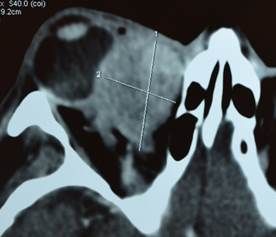

Enfermedad distiroidea de la órbita

La enfermedad de Graves u oftalmopatia tiroidea es una enfermedad autoinmune que afecta principalmente a pacientes femeninos jóvenes generando inflamación y expansión de la grasa orbitaria y desplazamiento ocular subsecuente (proptosis) aunque sus manifestaciones pueden ser múltiples incluyendo ojo rojo, lagrimeo, sensación de basura, fotofobia, dolor, visión doble e inclusive ceguera (más frecuentemente en pacientes arriba de la quinta década de la vida). Si bien la oftalmopatía suele estar precedida por un cuadro de hipertiroidismo, es frecuente observar diversos estados tiroideos en los pacientes. Algunos de los factores de riesgo más importantes para el desarrollo y progresión de esta enfermedad son el tabaquismo y el uso de yodo radioactivo. Su diagnóstico es clínico corroborándose con diversos estudios como pruebas de función tiroidea con anticuerpos, tomografía computada y campo visual.

Su tratamiento depende del grado de afección (severidad) y actividad inflamatoria. Los esteroides sistémicos y lubricantes oculares representan una opción eficaz aunque los anticuerpos monoclonales empiezan a posicionarse entre las opciones terapéuticas más novedosas . El manejo multidisciplinario entre oftalmólogo, endocrinólogo y reumatólogo representa la mejor forma de evitar complicaciones graves asegurando una resolución de la enfermedad más rápida y con menos secuelas.